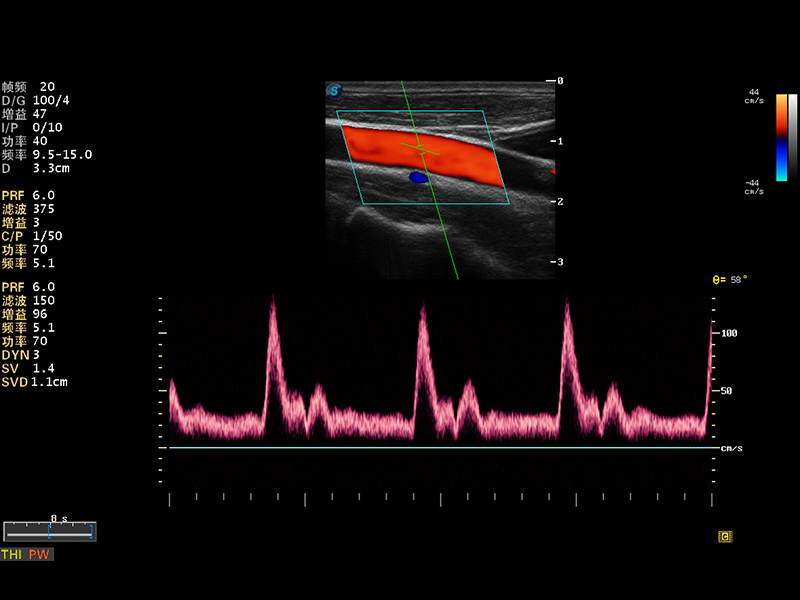

便携式彩色多普勒超声诊断仪

S8 EXP便携式彩色多普勒超声诊断仪是玖鼎集团研发的高端全身应用型便携彩超。高通道的VIS平台融合可视化(Visual)、智能化(Intelligent)和人性化(Smart)的特点,配以玖鼎集团自主研发生产的探头大家族,使您能够快速、准确的获得病人信息,提高工作效率的同时减轻疲劳。